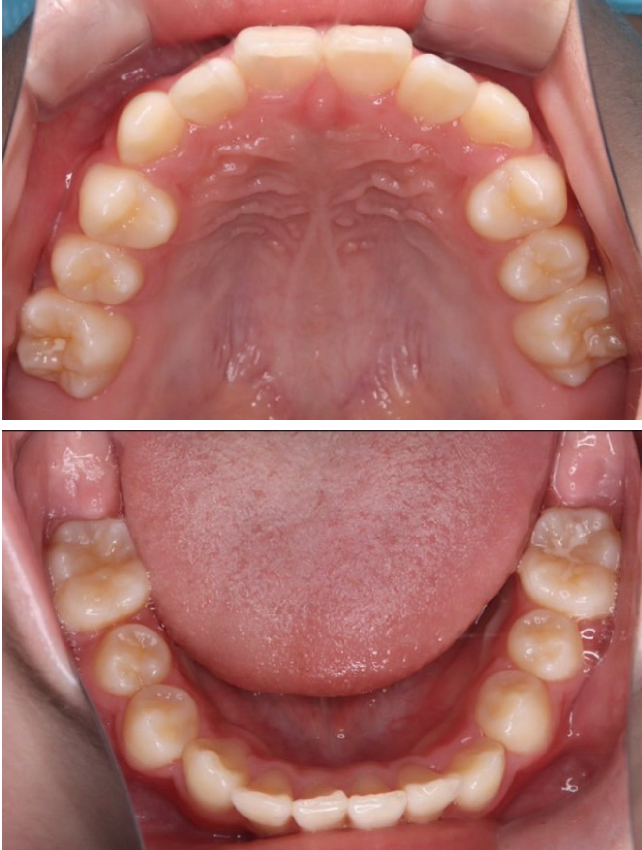

当院の症例

CASE